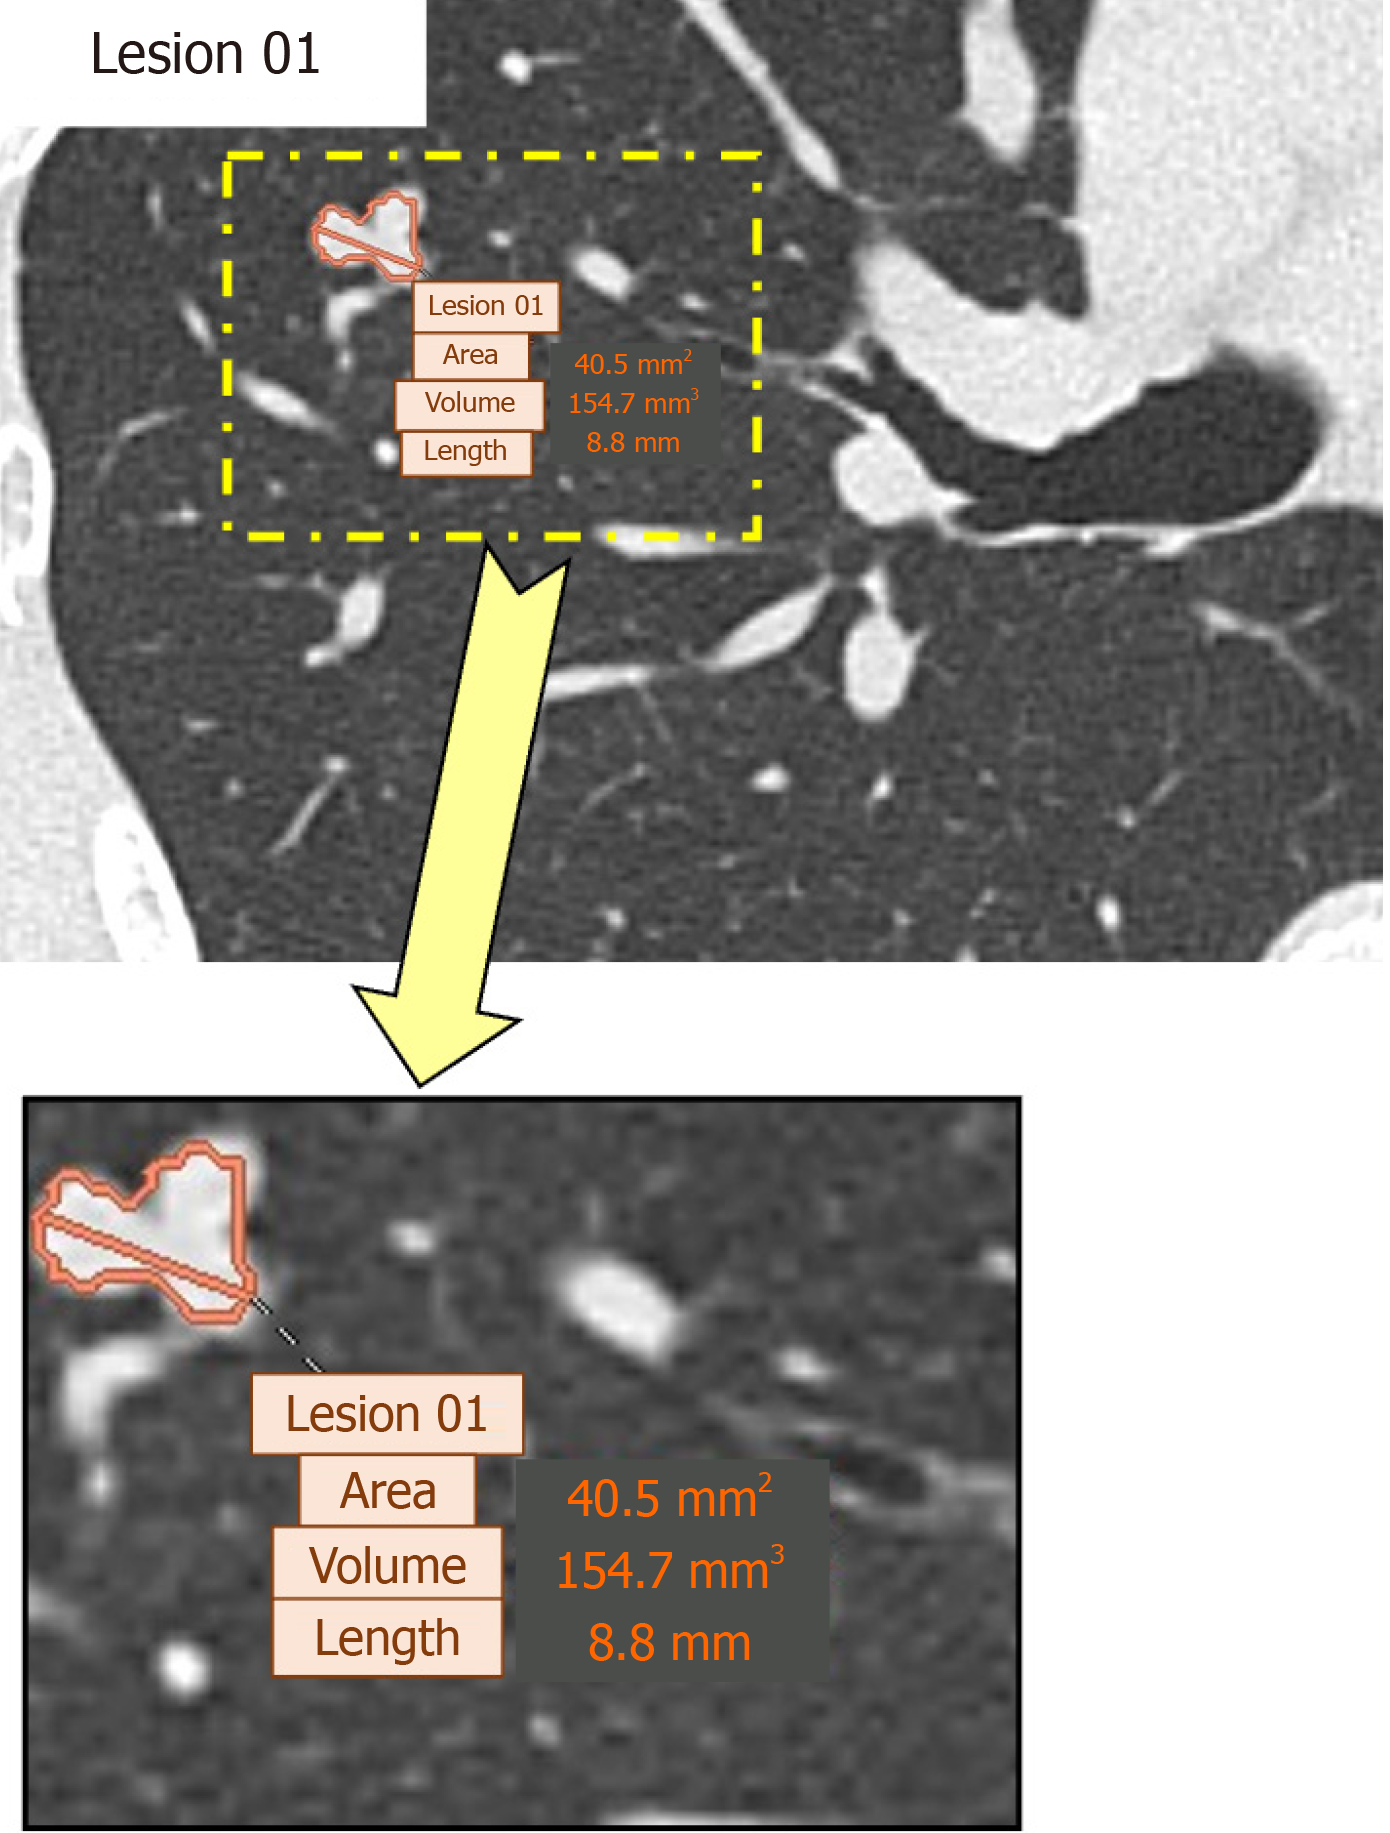

For analysis, the CAD system automatically processed axial CT images reconstructed at a slice thickness of 1 mm and highlighted potential lung nodule locations (Figure 2). The system provided quantitative measurements of the detected lesions, including area, volume, and maximum length; among these parameters, lesion volume and maximum length were recorded for analysis.